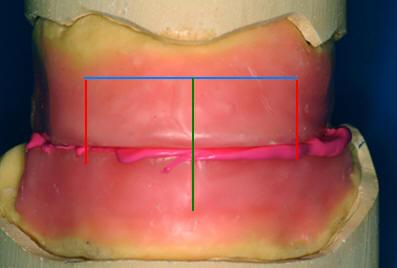

4- Con el paciente mordiendo suavemente los

rodetes marque las referencias necesarias para la elección de los

dientes:

- La línea media, (en color

verde) Ver fotografías y gráfico derecha

- Líneas caninas, (en

color rojo) es la línea perpendicular al plano de oclusión

que pasa por el borde externo del ala de la nariz de nuestro

paciente y por ende la distancia "ínter canina

o DC" que nos determinará el ancho

de los dientes anteriores, medida desde las cúspides de los caninos.

- Línea de los cuellos dentarios.

(en color celeste)

- Plano oclusal.

(en color azul)

- La distancia entre la línea de los cuellos dentales y el plano

oclusal nos determinará el alto de los dientes antero superiores

|